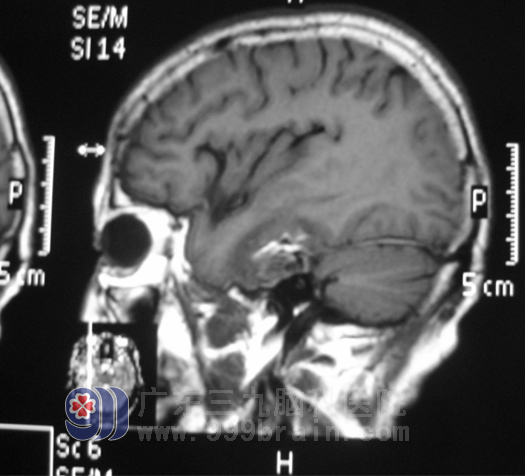

手术很成功,术后第十天,卢阿姨的身体恢复良好,无发热,无头痛、头晕,无恶心、呕吐,无肢体乏力,大小便正常。体查一切正常。http://www.999brain.com/

术后